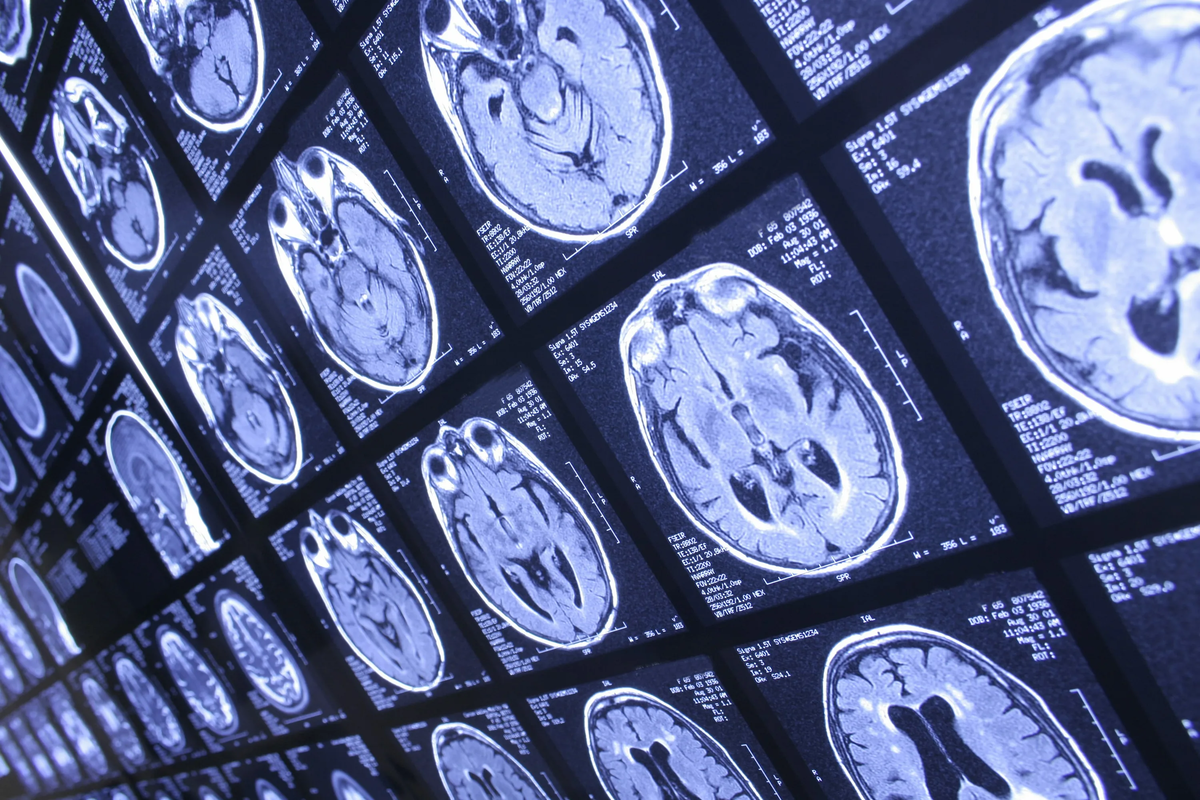

Проблема диагностики очагов демиелинизации у пациентов 50+

Если у человека есть диагноз, и картина МРТ со свежими активными очагами соответствует ему, то искать других объяснений очагов демиелинизации вроде как и не надо. Ну, это вот то самое «правило зебры», которое любят повторять в сериалах: если ты слышишь стук копыт, то представляй лошадь, а не зебру. И это правило работает в целом, но только в случае:

То есть, нельзя просто посмотреть на визуализацию мозга пациента, и сказать: ну у него рассеянный склероз, вот потому у него свежие очаги. Нужно врачу сравнить другие данные обследование и сделать вывод: соответствует картина МРТ демиелинизации при рассеянном склерозе или нет. Это особенно важно для пациентов 50+, так как после этого возраста сильно возрастает риск обретения дополнительных болезней.